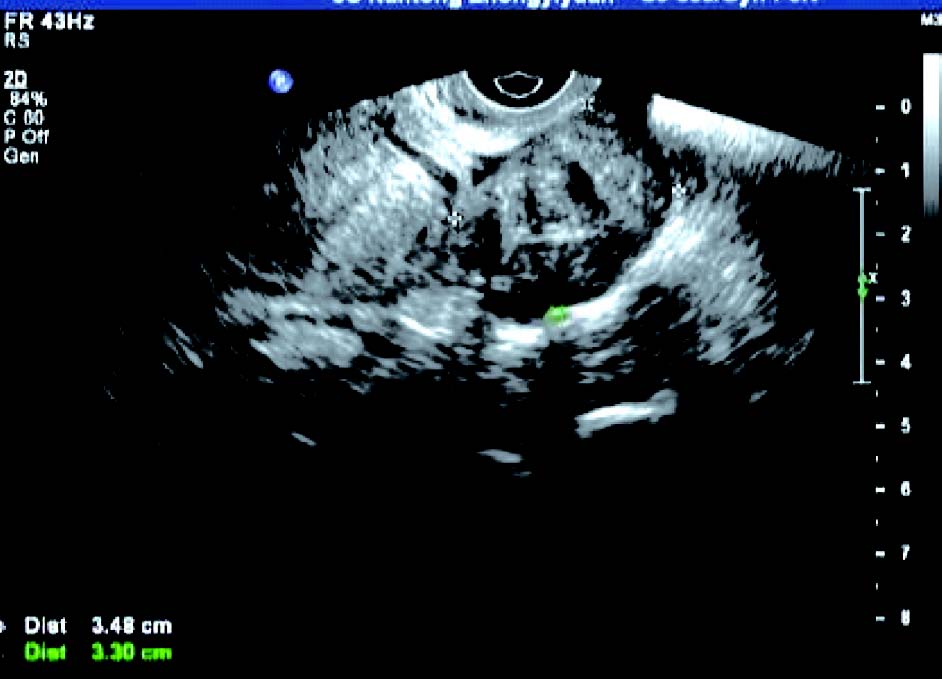

3. 黏膜下肌瘤

子宫内膜变形或缺损,内膜下肌层可见低回声结节突向宫腔,肌瘤完全突入宫腔时,宫腔内显示实性占位,但肌瘤与宫腔内膜间有裂隙,显现“宫腔分离征”。CDFI 检测:瘤体周边呈环状或半环状血流信号,内部呈条状血流信号。